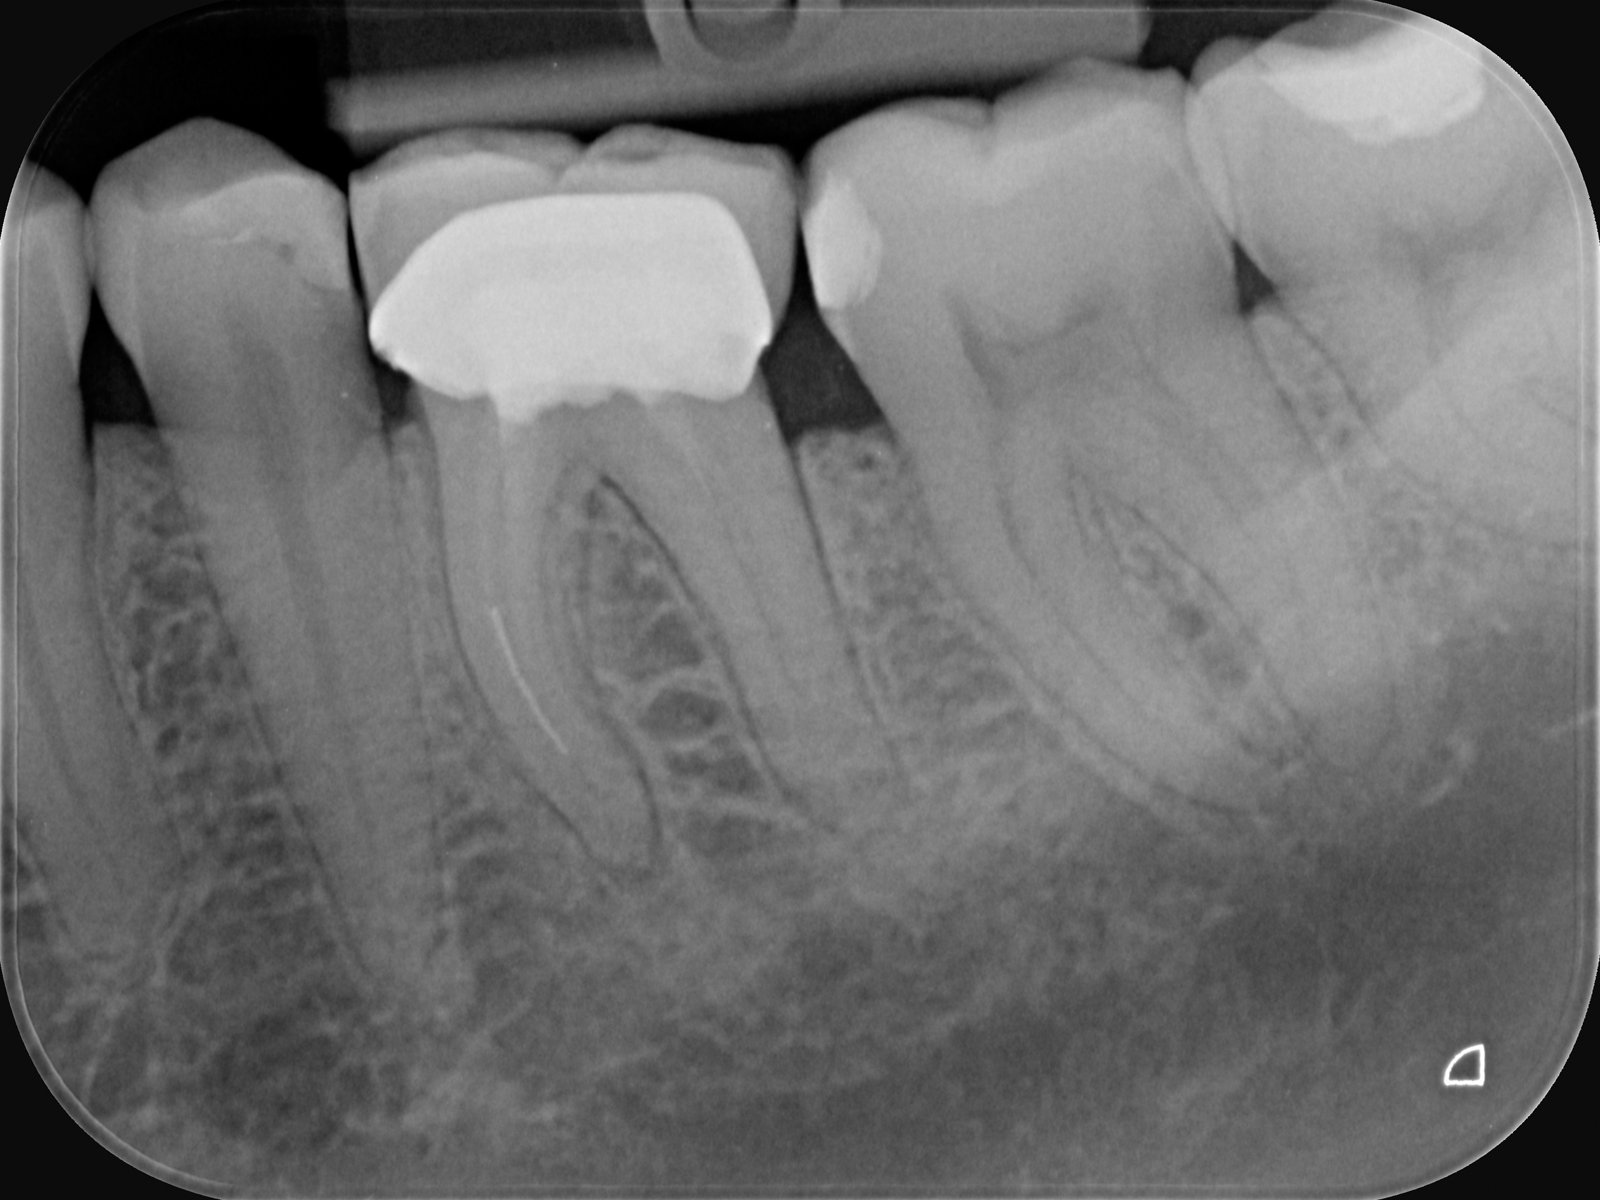

At Ashtead Dental, we are experienced in managing complex root canal cases, including the safe handling of a broken file during treatment. A broken file is a rare but recognised complication that can occur when a small instrument used to clean the root canal separates and becomes lodged inside the canal.

While a broken file does not usually cause pain or immediate harm to the tooth, it can interfere with thorough cleaning and disinfection, which are critical to the long-term success of root canal therapy. Our team is fully equipped with advanced tools and techniques to assess and manage this situation with precision and care.

If the broken piece is located deep within the canal (often near the tip of the root) and the tooth is not showing signs of infection, it may be safer to leave it in place and monitor the tooth over time.

Our clinicians are skilled in handling challenging endodontic cases and use high-powered magnification, digital imaging, and precision tools to plan and carry out the safest, most effective treatment. Each case is assessed individually to determine whether the file should be removed or monitored, always keeping your long-term tooth health in mind.